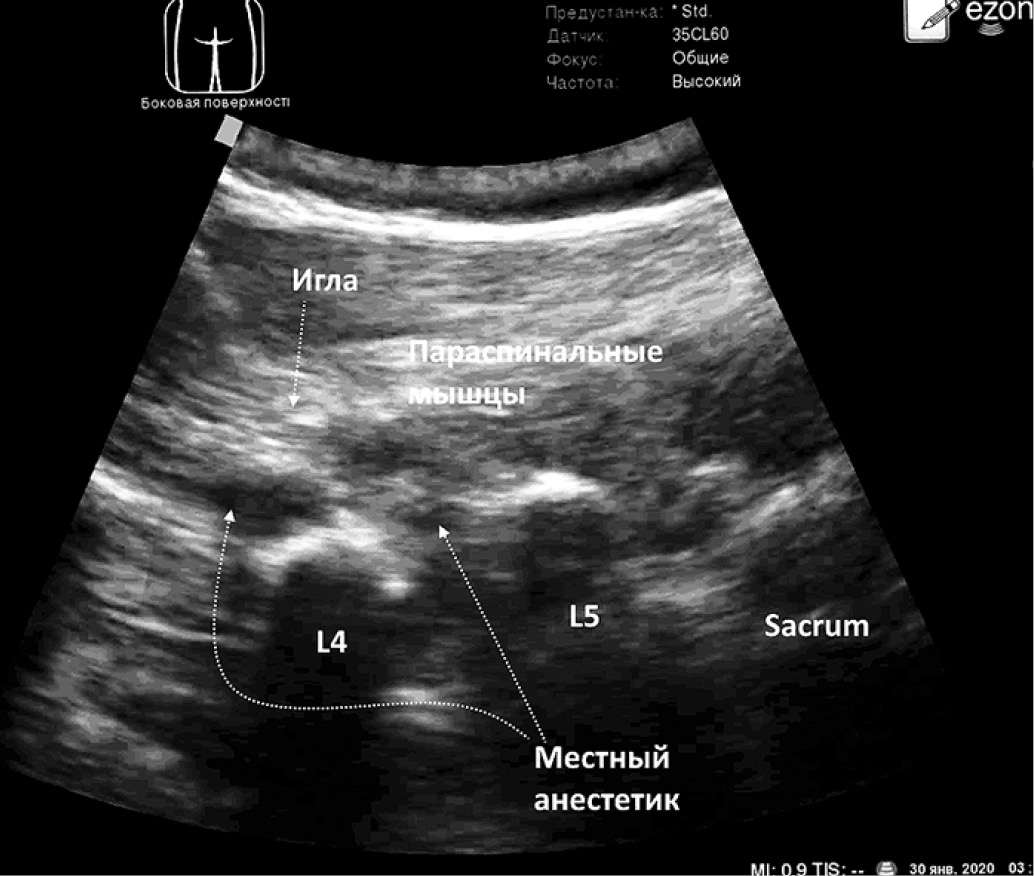

После верификации поперечного отростка L4 над гиперэхогенным поперечным отростком верифицируется разгибатель (выпрямитель) спины. Игла 22 G продвигается в кранио-каудальном направлении (in plane) к поперечному отростку, упираясь в него, производится гидродиссекция путём введения местного анестетика, открывая нейрофасциальное пространство разгибателя спины (рис. 3).

Рис. 3. Сонографические ориентиры блокады мышцы, выпрямляющей спину на поясничном уровне (рисунок авторов)

Fig. 3. Sonographic landmarks of the blockage of the muscle straightening the back at the lumbar level (authors’ drawing): 1 – needle, 2 – paraspinal muscles, 3 – sacrum, 4 – local anesthetic, 5 – transverse process L4